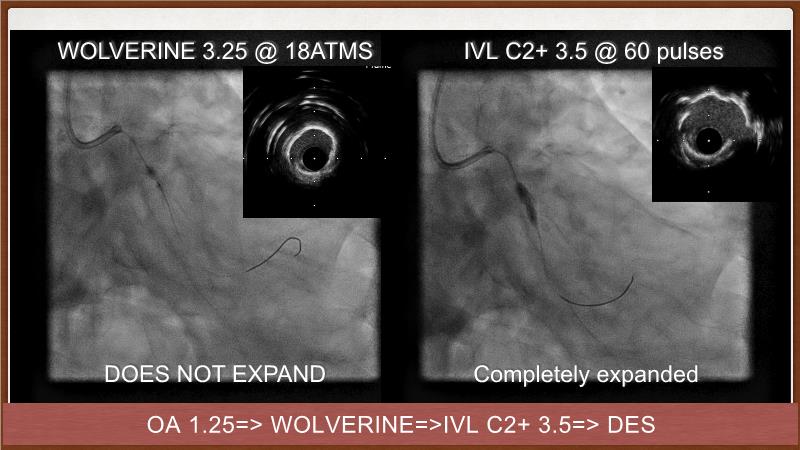

This session explores the challenges of treating calcified lesions during percutaneous coronary intervention (PCI). Learn how calcium can impede stent deliverability and expansion, potentially leading to thrombosis and restenosis. Discover the innovative Shockwave IVL technology, which uses sonic pressure waves to fracture calcium without harming surrounding tissues. The discussion also covers the ongoing challenges of calcified nodules, the importance of intracoronary imaging, and how a layered approach with multiple devices can enhance treatment outcomes. Finally, see how the IVL Shockwave C2+ device facilitates targeted energy delivery for effective PCI.

- To understand the science behind the mechanism of action of intravascular lithotripsy (IVL) for the treatment of calcified lesions

- To learn about the role of intravascular imaging (IVI) in the treatment of calcific lesions

- To uncover practical tips and techniques for IVL in challenging calcified lesions: diffuse, ostial LAD bifurcations and eccentric/calcified nodules